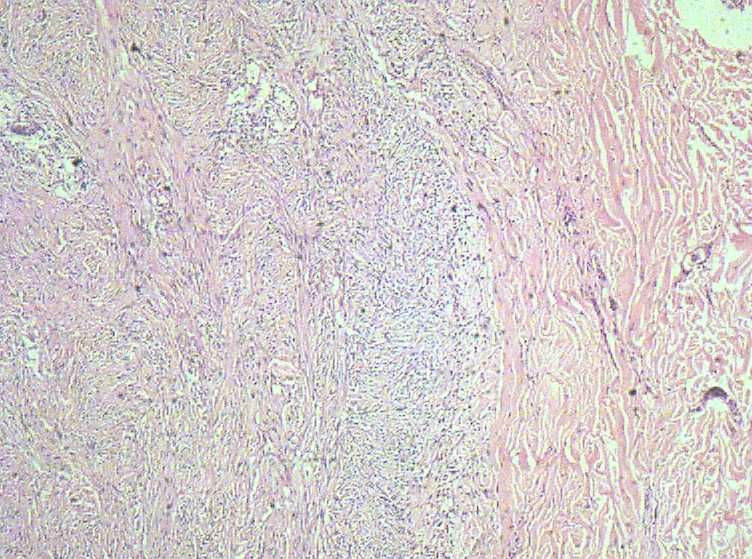

女40岁,发现乳房皮肤表面一年多。

肉眼:不整形组织1.5*1*0.5一侧见皮肤或一侧可见脂肪,切开内一小结节触之稍韧。

• 乳房皮肤表面小结节  请会诊!图4

图4

倾向于皮肤纤维瘤。

皮肤纤维瘤

良性病变。

炎症后的瘢痕结节或者纤维组织瘤样增生?